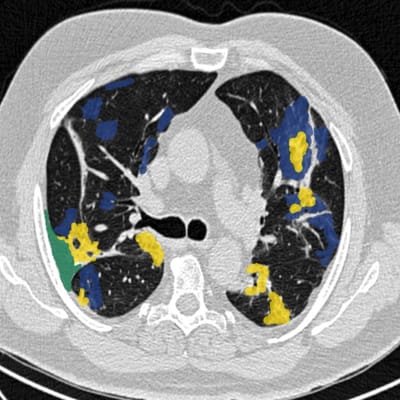

Experience the future of image segmentation with our user-friendly tool designed by radiologists, for radiologists. Experience effortless workflows and improved accuracy with our radiology and gaming-inspired controls.

We provide segmentation services for CT or MRI datasets. Our radiologist-validated results use modern AI models to produce precise annotations in the form of masks, volumes, or 3D models/meshes in any file format. This service is available for a fee.

We are open to collaborating on research and are dedicated to advancing the field. To support this effort, we are creating open-access segmentations whenever possible.